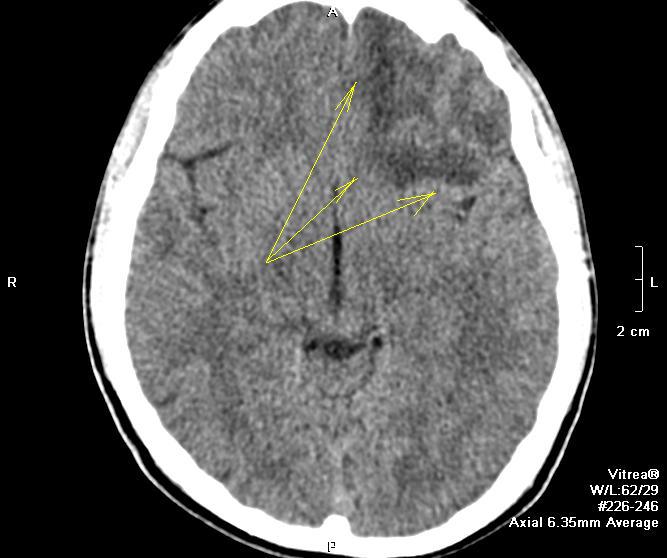

Прошу простить за вопрос дилетанта. Чем обусловлена более высовая "интенсивность" в лобной части, помеченная желтыми стрелками.

По всей видимости, очаг ушиба мозга по типу противоудара

Для КТ-шников, это как "воздушная бронхограмма" для насУлыбается. Ушиб головного мозга.

В лобной и височной долях контузионные очаги. Мы ползуемся классификацией Корниенко.

Вернее будет участок неравномерно пониженной плотности.